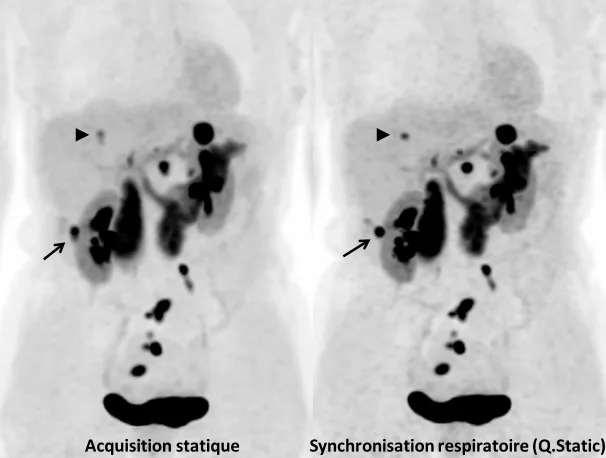

Une étude au CEA-SHFJ a montré l’intérêt d’utiliser en routine la synchro­nisation respiratoire avec ceinture pneumatique au cours de bilans oncologiques de routine [28, 29]. Chez des patients atteints de lésions pulmonaires, médiastinales ou hépatiques, en TEP, un tiers des lésions était significativement affecté par le flou respiratoire (flou perceptible visuellement). Au sein de ces lésions visuellement affectées par le mouvement respiratoire en TEP, la correction du mouvement respiratoire (méthode Q.Freeze, basée sur un recalage non rigide des phases du cycle), s’est avérée efficace dans la quasi-totalité des cas (97 %), conduisant à une disparition partielle ou complète du flou visuel, et à une augmentation significative du SUV (augmentation médiane du SUVpeak de 9,4 %) (Fig. 5). Les corrections de mouvement respiratoire peuvent donc avoir un impact sur la quantification et modifier en particulier la classification des réponses thérapeutiques en oncologie.

Figure 5. Tumeur neuro-endocrine différenciée du grêle. Bilan de réévaluation par TEP/IRM à la Fluoro-DOPA. Comparaison des acquisitions sans et avec synchronisation respiratoire. L’examen montre des lésions tumorales ganglionnaires pelviennes, ainsi que plusieurs lésions hépatiques. La lésion hépatique indiquée par une flèche apparaît plus nette sur l’image synchronisée, avec moins de flou. La lésion indiquée par une tête de flèche, nettement visible sur l’image synchronisée, apparaît presque comme deux lésions contiguës sur l’image non synchronisée. La synchronisation respiratoire a pour avantages de diminuer le flou dans les images, d’améliorer le recalage avec l’IRM, et d’améliorer la quantification de la fixation par le SUV